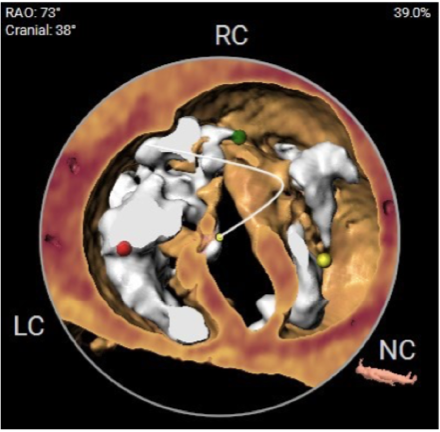

2)患者主动脉根部结构复杂,为Type 2型二叶瓣畸形,左右对合缘、右无对合缘处均可见钙化融合嵴,瓣环平面可见严重钙化,左冠窦底钙化灶延伸至左室流出道,且左室腔小。